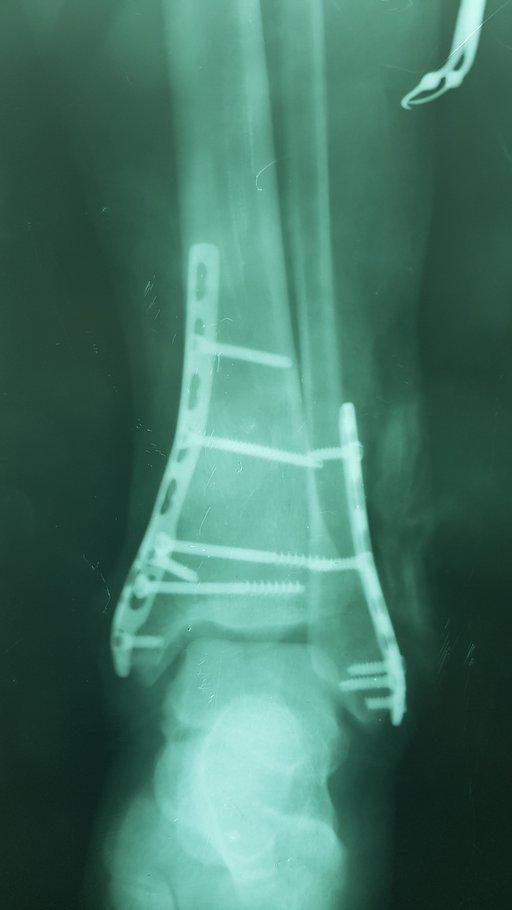

Хвора Л. 45 р. отримала травму в побуті на сходах. Через 30 хв після травми доставлена родичами в травмпункт КНП ТМКЛШД. Оглянута травматологом травмпункту, направлена на рентгенографію. Згідно даних рентгенограм встановлено діагноз: Закритий с\3 – н\3 лівої м\гомілкової кістки зі зміщенням уламків. Закритий перелом внутрішньої кісточки та заднього краю лівої в\гомілкової кістки зі зміщенням. Розрив ДМГС зліва. Підвивих стопи до зовні та до заду.

Хворій накладено тимчасову фіксацію та направлено в приймальне відділення КНП ТМКЛШД. Хвора повторно оглянута травматологом стаціонару. При огляді відмічається незначний набряк, біль, порушення функції н\кінцівки. Встановлено діагноз : Закритий с\3 – н\3 лівої м\гомілкової кістки зі зміщенням уламків. Закритий перелом внутрішньої кісточки та заднього краю лівої в\гомілкової кістки зі зміщенням. Розрив ДМГС зліва. Підвивих стопи до зовні та до заду

Хворій рекомендовано оперативне втручання, на яке хвора дала згоду. При госпіталізації проведено необхідні інструментальні та лабораторні методи обстежень та огляд консультантами (терапевтом та анестезіологом). В екстреному порядку хворій проведено оперативне втручання – Відкрита репозиція з МОС перелому зовнішньої кісточки стягуючим гвинтом та нейтралізуючою пластиною LCP та відкрита репозиція з МОС внутрішньої кісточки спицею та гвинтом. Після оперативного втручання хвора переведена в палату. З 2-3 доби хворій дозволено активні рухи у г\ступневому суглобі без навантаження на ліву н\кінцівку. Шви знято на 11 добу, хвора в задовільному стані з наданими рекомендаціями щодо тактики подальшого лікування виписана з травматологічного відділення.